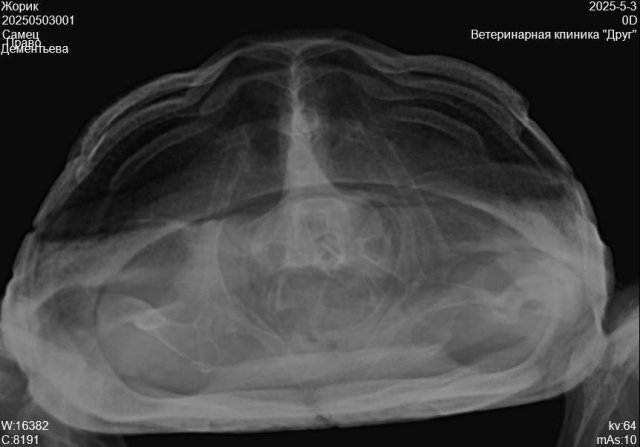

Пермь. Сухопутная черепаха. Террариум самодельный, длина 85см, ширина40, высота 40.лампа накаливания обычно работает в зоне прогрева 12часов.ультрафиолетовая лампа тоже 12часов    reptispa desert 10.0 uvb10. Грунт кокосовый субстрат перемешаный с речным песком. Температура под лампой 30-32гр.Летом кормим травой одуванчик, подорожник, клевер. Зимой салат, кабачок, огурец. Живёт у нас 9лет.вес 400гр., панцирь по длине 15см.заболела в конце марта. Чихала, был насморк, вялость. Лечили энрофлон аскорбинка, кальций, элеовит это было по рекомендации онлайн ветеринара. Потом еще назначали ингаляции с флуимуцилом это уже назначили в клинике друг, врач Бажина.Сейчас при еде выходит пена изо рта и носа.

20250503001_Жорик_Дементьева_20250503092325236.jpg

20250503001_Жорик_Дементьева_20250503092325086.jpg

20250503001_Жорик_Дементьева_20250503092324931.jpg

лечение когда закончили и снимки эти когда делали?

Лечение закончили в середине мая ингаляции с флуимуцилом. Рентген делали после лечения антибиотиком, перед лечением ингаляциями

@Галина М по-хорошему вам нужно снова на очный приём и делать новый рентген. Это очень сильная пена и даже если это из желудка - это очень не нормально. А из лёгких и подавно.